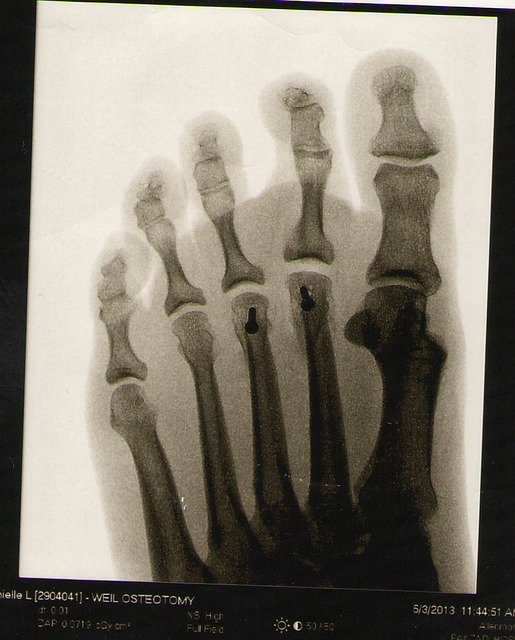

Esqueleto apendicular

Published in Qué es el esqueleto apendicular